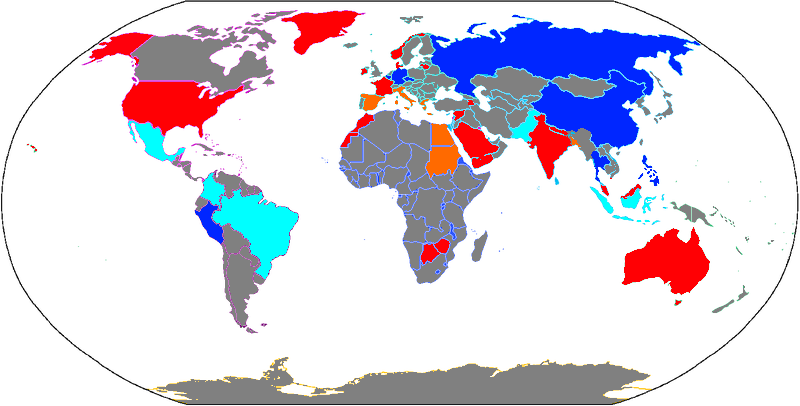

لكنه في نفس الوقت ممنوع في الولايات المتحدة و الخليج و انجلترا و الهند . سبب المنع انه له مخاطر نادرة بس خطيرة، زي Agranulocytosis (نقص في كرات الدم البيضا) أو التهاب الكبد الحاد . النهارده هنحاول نقارن الفايدة والضرر و نتعرف على واحد من أكثر الأدوية المختلف عليها و المثيرة للجدل في العالم .

دول كتير قررت سحب الدوا من الأسواق و الغاء التصريح ببيعه وكان من الدول دي السويد و الولايات المتحدة و انجلترا . في بعض الدول دي نوفالجين استخدامه مقتصر على العلاج البيطري فقط و بعضها منعه حتى للحيوانات

ولكن البعض الاخر شاف ان الاعراض الجانبية في الNSAID مثلا مش اقل خطورة و نسبة الاصابة بالنزيف المعوي معاهم أعلى ودا طبعا ممكن برده يكون قاتل . كمان نسبة حدوث الاثار الجانبية بشكل عام مع الميتاميزول اقل بكتير جدا منها في ال NSAID و تعارضه مع الادوية التانية اقل بكتير . الدول دي قررت تحافظ على التصريح مع وضع ضوابط على البيع . في المانيا مثلا تم حصره في حالات الام العظام و العضلات أو الاورام . غير كدا بيتوصف فقط كاضافة لو المسكن العادي مجابش نتيجة كافية.

في 2024، وكالة الأدوية الأوروبية (EMA) بدأت مراجعة شاملة لنوفالجين بعد تقارير عن وفيات مرتبطة بAgranulocytosis في إسبانيا وفنلندا. الهدف إنهم يقرروا لو الدوا هيستمر، يتعدل، ولا يتشال من السوق. المراجعة انتهت انه مش هيتمنع ولكن هتزيد القيود على وصفه

في مصر و كتير من دول أمريكا الجنوبية ، نوفالجين متوفر بسهولة في الصيدليات والمستشفيات، ومن غير قيود صارمة أو متابعة مستمرة، وده بيزود مخاطر سوء الاستخدام.

من الغريب انه برغم انه ميتاميزول ممنوع في الولايات المتحدة الا انه أغلب المهاجرين من امريكا اللاتينية متعودين عليه و بيستخدموه بدون اشراف طبي و بيجيبوه معاهم من بلادهم ، دا بيخلي الاصابة بالأعراض الجانبية النادرة ظاهرة بتحصل في أمريكا رغم كونه ممنوع.